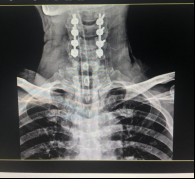

(術(shù)前拍片)

在完善了各項(xiàng)相關(guān)檢查后,張阿伯被診斷為:頸部脊髓損傷,不完全癱瘓及全身多處骨折,我院脊柱科主任戈才華建議其入院并接受頸后路頸椎融合手術(shù)。